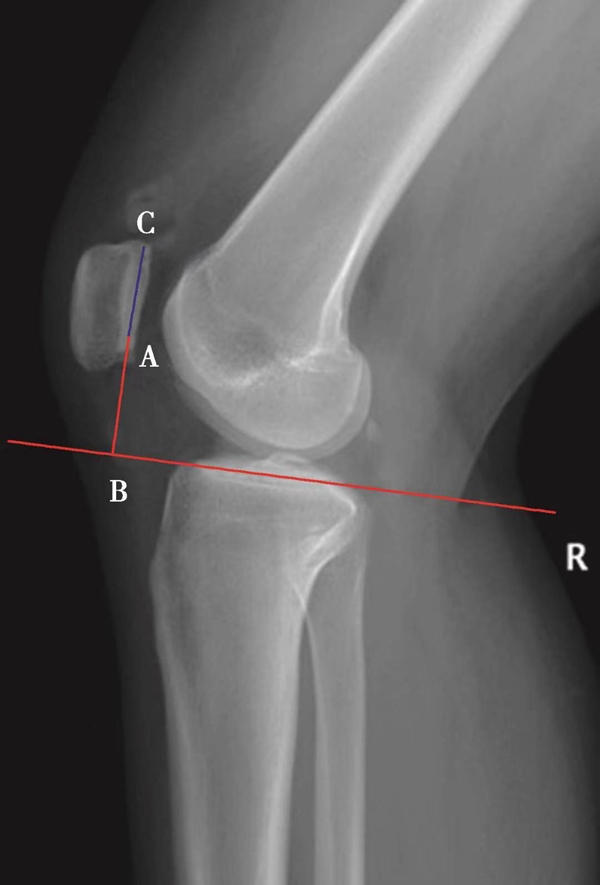

常用的评估髌骨高度的方法包括Caton指数、Insall-salvati指数及Blackburne-Peel指数。

(1)Caton指数>1.2提示高位髌骨(图3),而<0.8提示低位髌骨。

体位:侧卧位屈膝30°。

如图示:AB为髌骨关节面最低点到胫骨平台轮廓前上角最短的距离,AC是髌骨关节面的长度。Caton指数=AB/AC(图1)。

图1

图2 Caton指数=AB/AC=1.10,为正常髌骨高度

临床工作中常常使用其来估计胫骨结节移位的效果。正常人的Caton指数=1,正常范围0.8~1.2(图2)。需要注意的是:术前规划胫骨结节需要移位的理论距离为AB-AC,这就是需要将胫骨结节向远端移位的最大距离。但在术中胫骨结节转移的距离往往要小于这个距离,避免因过度移位造成医源性的低位髌骨。

此外,部分患者的胫骨前上缘难以确定。若患者行胫骨结节转移术后,Caton指数可能无法评估。对全膝关节置换术后,也无法使用Caton指数进行评估。